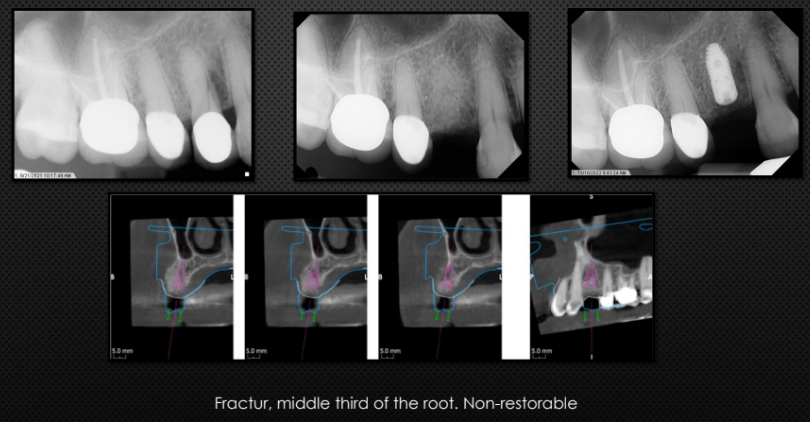

Facial fenestration, dehiscence, loss of facial bone, infection around the tooth